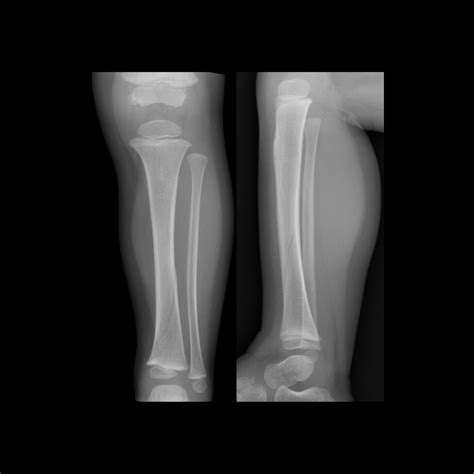

Management of a dislocated talar dome fracture with ankle

Management of a dislocated talar dome fracture with ankle ...